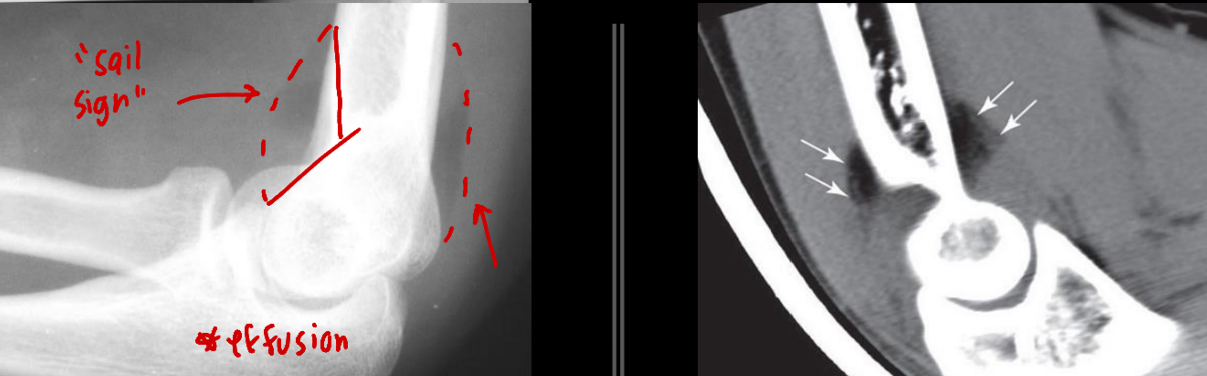

Soft tissue: What are the components you are examining?

• Enlarged, displaced, elevated, blurry → indicates trauma nearby

Where can you observe a “sail sing” and what does it indicate?

Disruption in the ANTERIOR fat pad, correlates to:

• Kids: Epicondyle/humeral fracture

• Adults: Radial head fracture

<p>Disruption in the <span style="color: red;"><strong><u>ANTERIOR </u>fat pad</strong></span>, <em><u>correlates </u></em>to:</p><ul><li><p>Kids: <mark data-color="red" style="background-color: red; color: inherit;">Epicondyle/humeral fracture</mark></p></li><li><p>Adults: <mark data-color="red" style="background-color: red; color: inherit;">Radial head fracture </mark></p></li></ul><p></p>